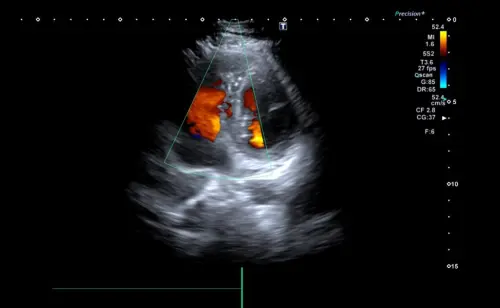

Эхокардиография — ультразвуковой метод диагностики, показывающий работу сердца в реальном времени. В отличие от ЭКГ, которая фиксирует электрическую активность, УЗИ визуализирует анатомические структуры: размеры камер сердца (их оценивают с учетом возраста и телосложения), толщину стенок миокарда, движение клапанов, характер кровотока.

Эхокардиография допплер измеряет скорость кровотока, выявляет регургитацию на клапанах сердца на узи, оценивает давление в легочной артерии. Процедура безопасна, не имеет лучевой нагрузки, можно проводить неограниченное количество раз.

Врач оценивает размеры камер — увеличение левого желудочка указывает на гипертрофию при гипертонии, расширение предсердий сопровождает мерцательную аритмию. Толщина стенок миокарда показывает, насколько сердечная мышца справляется с нагрузкой. Фракция выброса сердца определяет процент крови, выбрасываемой за одно сокращение — норма 55-70%. Что видно на узи сердца в допплеровском режиме — направление и скорость кровотока, обратные токи через клапаны, сужения.

Мы используем ультразвуковую систему Mindray Resona I8 на платформе ZST+ с функцией цветного допплеровского картирования. Аппарат дает изображение высокого разрешения, что позволяет визуализировать небольшие дефекты перегородок и минимальную регургитацию на клапанах. Технология тканевого допплера оценивает движение самой сердечной мышцы — это помогает выявить диастолическую дисфункцию на ранних стадиях. Все исследования проводятся по международным протоколам с измерением стандартизированных параметров.